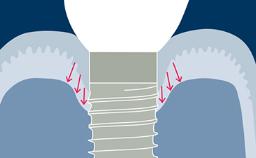

A terapia com implantes provou ser uma modalidade de tratamento bem-sucedida, aplicável a uma ampla gama de indicações clínicas para substituição dental. Em sintonia com o amplo uso da terapia com implantes, as demandas sobre os resultados estéticos também aumentaram. Este módulo tem como objetivo auxiliar os clínicos na avaliação e discussão desses resultados com seus pacientes.

- definir estética em implantes

- avaliar os resultados estéticos

- identificar casos de comprometimento estético

- Reconhecer complicações estéticas